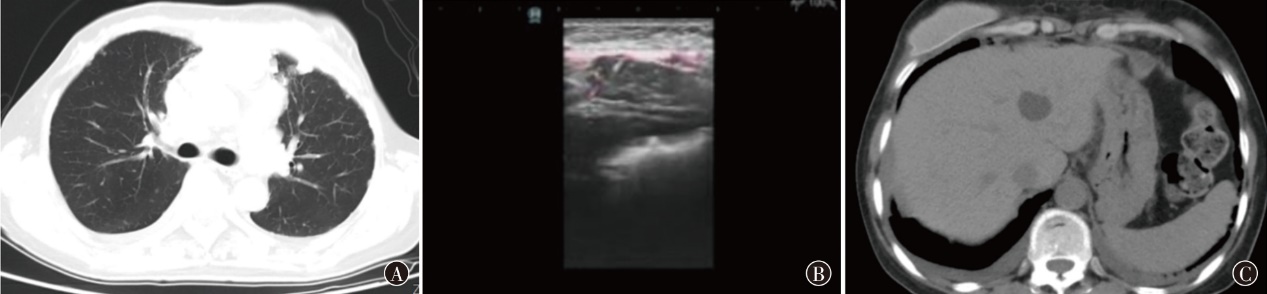

戈沙妥珠单抗于2022年6月正式被国家药品监督管理局批准上市,作为作用于Trop-2靶点的抗体偶联药物,为晚期三阴性乳腺癌患者带来了新的治疗选择。现报道1例晚期三阴性乳腺癌患者在病情出现进展时使用戈沙妥珠单抗治疗后情况,病情变化达到稳定,患者获益较为明显。